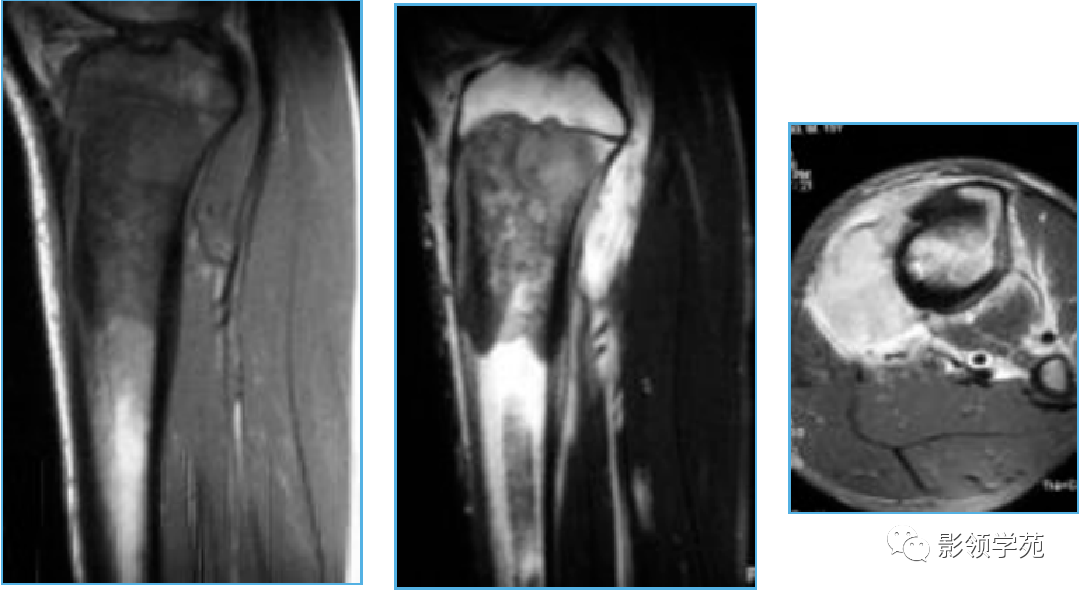

骨肉瘤osteosarcoma

10种类型骨肉瘤影像学诊断

5 分钟学会诊断骨肉瘤

5 分钟学会:骨肉瘤的诊断要点